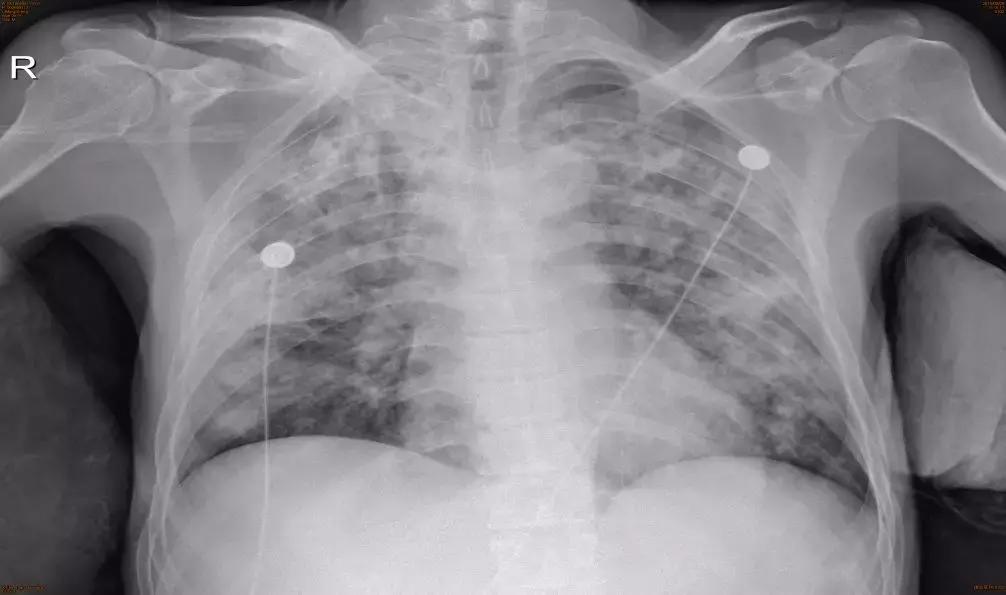

2018-02-08本院,床边胸片如下:

血常规:白细胞计数 27.04x10^9/L,中性粒细胞% 91.6%,血红蛋白 123g/L,血小板计数 284×10^9/L;

血生化:葡萄糖 17.55mmol/L,白蛋白 20g/L,钾2.49mmol/L;

血气分析:PH7.50,PO2 7.16kpa,PCO2 4.50kpa,HCO3-25.4mmol/L。

注:在临床中,曲霉菌感染也可以使白细胞升高,不是白细胞升高只是细菌感染。

于2018-02-01转入我院住院治疗,入院后予以病重,吸氧,监护,其痰液粘稠,肺部广泛哮鸣音,气促明显,病情进展迅速,血象高,血气提示氧合指数200mmHg。

予以泰能、利奈唑胺广谱覆盖抗感染,伏立康唑抗真菌;胸腺肽提高免疫力等综合治疗,后查痰检高通量测序结果显示「仅有曲霉菌生长,无其他细菌生长」,停用抗细菌药物,并继续伏立康唑抗真菌,症状改善慢,后联合使用两性霉素B后好转,口服伏立康唑序贯。

2018-03-02日治疗后临床好转,复查胸部CT:多发病灶,多发坏死空洞。